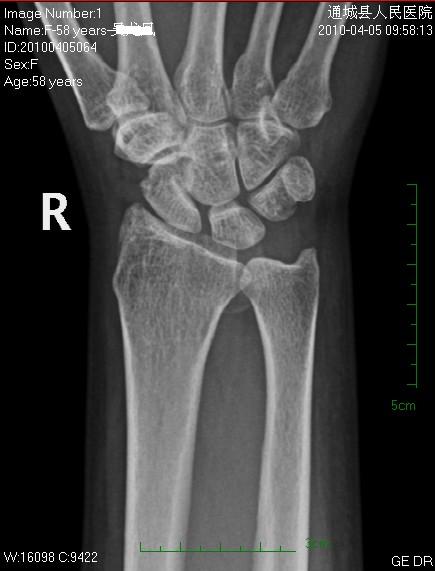

女性58岁,右腕肿痛就诊。平时右腕间断性疼痛,近来加重。

平片见桡前软组织内一密度增高、边缘光整块影

后三张是透视转动下点片放大。

片含诸构成骨无明显骨质破坏,软组织稍肿胀。片示软组织内异常密度影个人考虑为纤维组织增生,伴局部皮肤呈癣样变。考虑:银屑病性关节炎。建议作进一步检查。

1、腱鞘囊肿;2、舟状骨骨折,是否有可能是创伤后软组织遗留下的某种改变。

我考虑腱鞘囊肿可能性大。另尺骨稍长,月骨、三角骨尺骨关节面密度减低。考虑尺骨撞击综合症